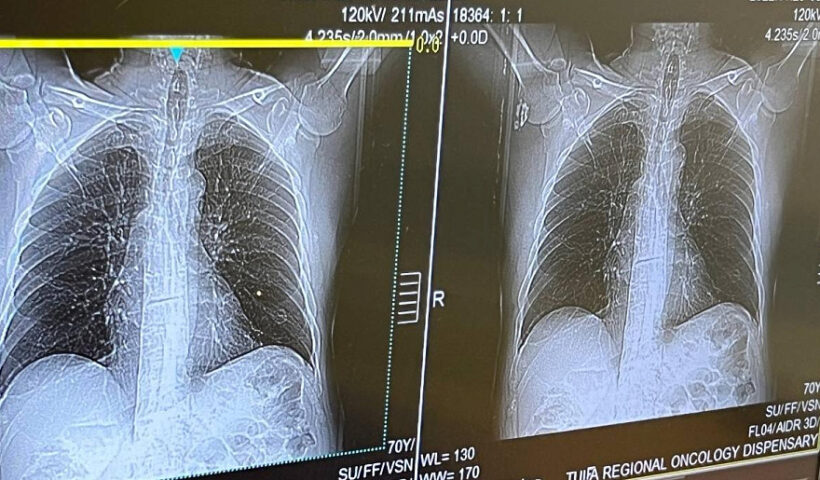

Роспотребнадзор сообщает о росте активности острых респираторных вирусных инфекций (ОРВИ) в России, при этом доминирующим штаммом гриппа является вирус А(H1N1)2009, который чаще других вызывает тяжелое течение заболевания и может приводить к легочным осложнениям, в частности, к пневмонии.

В ведомстве отмечают, что грипп, вызванный этим штаммом, способен быстро прогрессировать и привести к тяжелым осложнениям в течение 24 часов. Пневмония является наиболее частым осложнением гриппа и составляет 65% от всех случаев, приводя к летальным исходам.